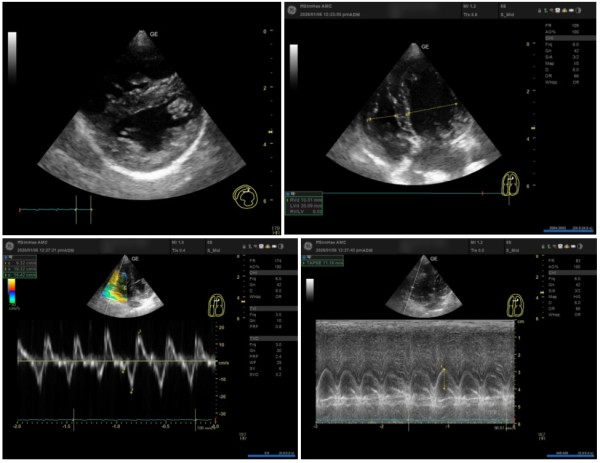

② RV(우심실)의 구조적 변화와 기능

우심실의 압력이 높아지면 좌심실을 압박하게 됩니다.

IVS Flattening (심실중격 평탄화): 우심실 압력으로 인해 좌심실이

'D자 모양'으로 눌리는 현상이 관찰되었습니다. (LV eccentricity index 변화)

Underfilling of LV: 좌심실로 들어오는 혈류량이 줄어들어 좌심실 크기가 작아진 상태입니다.

RV 기능 지표: S' 12.32cm/s, TAPSE 11.18mm 등으로 우심실의 수축력을 정밀 평가하였습니다.

3b5a6cb0f0735f89df35c2e207e2d7ba_1776391177_548.jpg